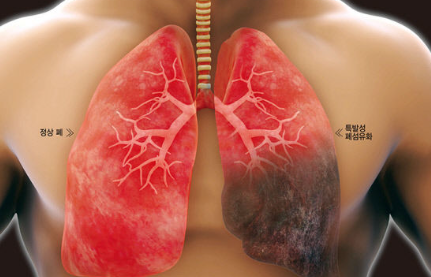

폐섬유증은 폐 조직이 점차 굳어지면서 호흡장애를 일으키는 질환인데요. 폐섬유화증은 폐섬유증의 한 종류로, 폐 조직이 딱딱해지는 현상을 의미합니다. 이러한 변화는 폐에 염증이 생겼다가 아무는 것이 반복되면서 마치 상처가 굳은살과 흉터를 만드는 것과 비슷한데요.

폐섬유증 대부분은 명확한 원인이 없는 특발성 폐섬유증이며, 평균 생존율은 확진 후 3~4년 정도로 알려져 있습니다. 따라서 호흡기 증상이 장기간 호전되지 않는다면 전문의의 도움과 빠른 치료가 시급합니다.